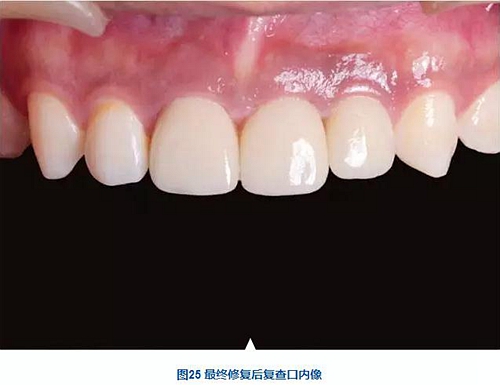

術(shù)后7個月,戴入最終修復體,紅白美學效果滿意。

種植體周圍骨水平穩(wěn)定,齦乳頭及齦高點位置穩(wěn)定,齦緣曲線形態(tài)理想,唇側(cè)軟硬輪廓良好,功能滿意,修復效果符合預期。

本病例在觀察期內(nèi),種植修復獲得了良好的軟硬組織美學效果和穩(wěn)定性?;颊邔χ委熜Ч麧M意。